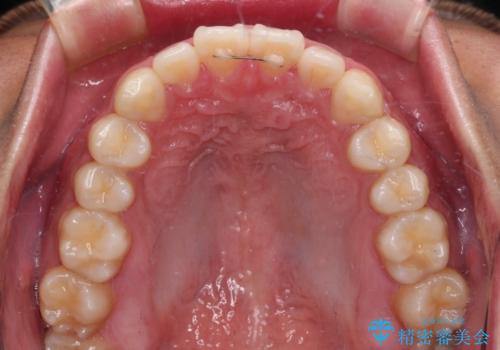

- 上下前歯の叢生を気にして来院された患者様です。

費用を抑え、期間もあまりかけずに治療をしたいとのことで、インビザライン・ライトを用いて矯正治療を行うこととしました。